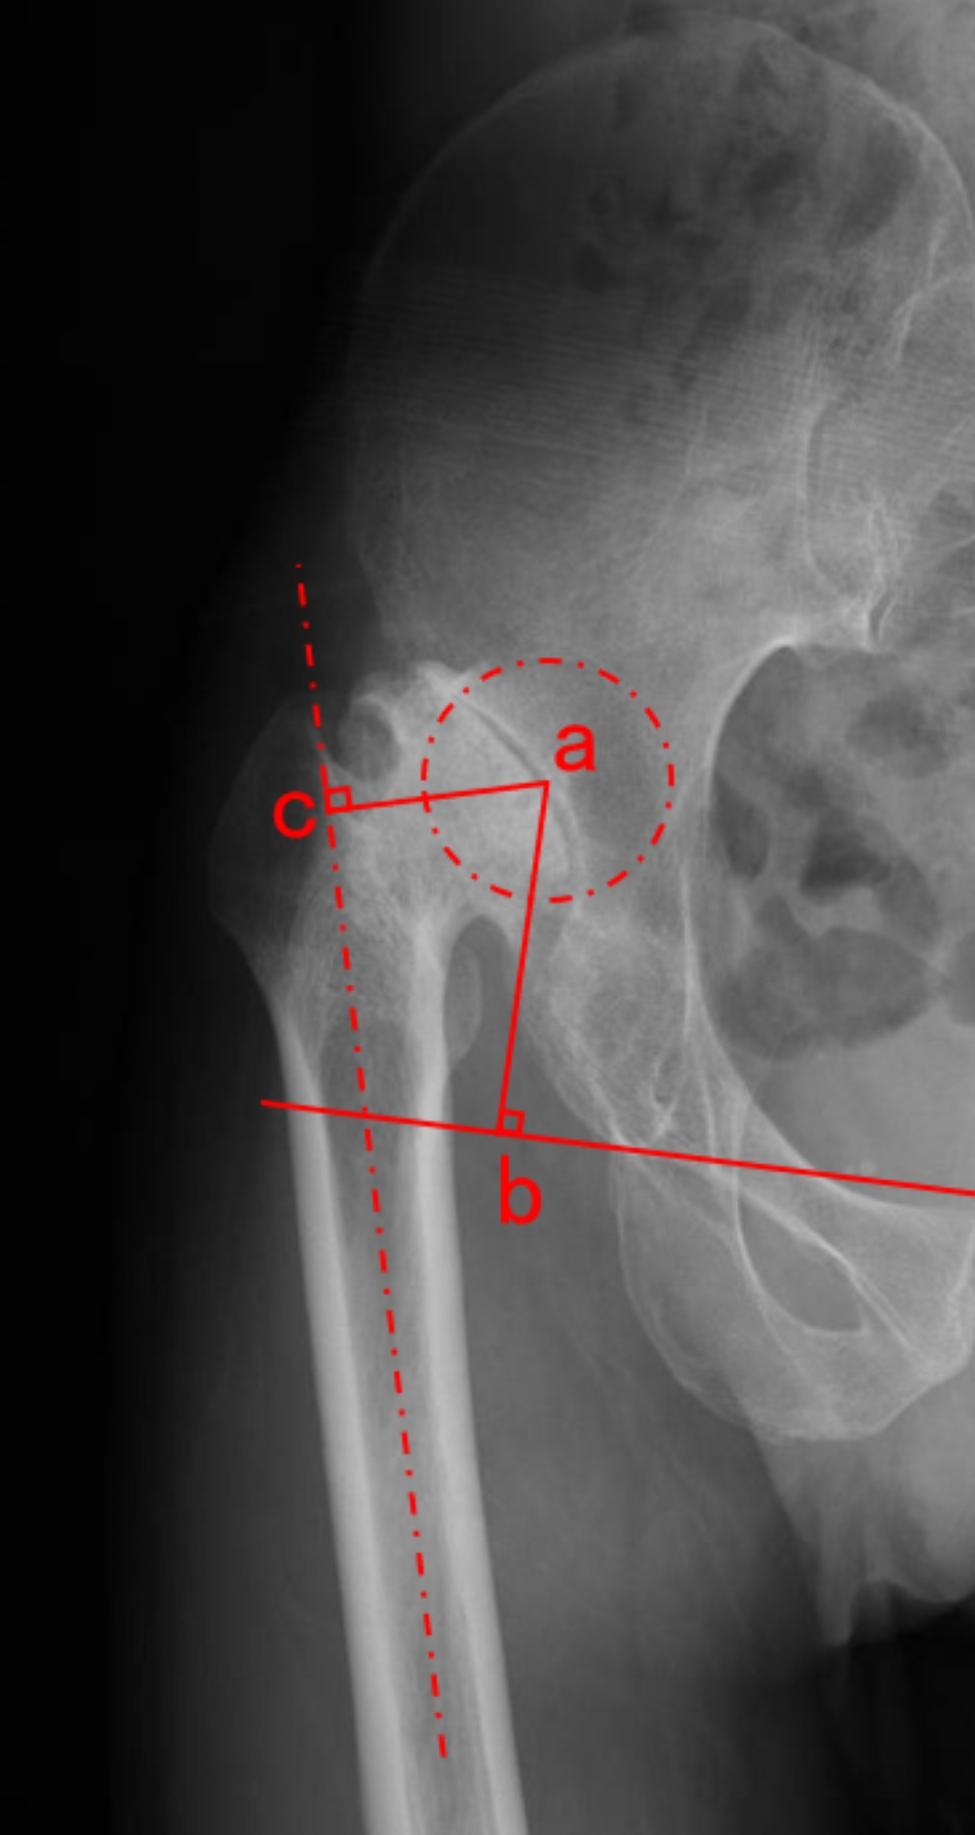

We identified 178 patients who underwent THA with SSO for high hip dislocation between November 2010 and April 2021. The consecutive cohort was analyzed by logistic regression to determine the effect of ICS on postoperative allogeneic blood transfusion (ABT) and to explore the associations between patient demographics, clinical and radiographic characteristics, preoperative laboratory examination, and surgical variables with the ability to generate adequate blood salvage to reinfuse.

In the consecutive cohort of 178 patients, cell salvage was reinfused in 107 patients (60.1%) and postoperative allogeneic red blood cell (RBC) transfusion within 3 days of implantation was administrated in 40 patients (22.5%). In multivariate analysis, the reinfusion of ICS (OR (95%CI) 0.17 (0.07-0.47)), center of rotation (COR) height ≥ 60 mm (OR (95%CI) 3.30 (1.21-9.01)), the length of SSO ≥ 30 mm (OR (95%CI) 2.75 (1.05-7.22)) and the use of drainage (OR (95%CI) 2.28 (1.04-5.03)) were identified as independent factors of postoperative allogeneic RBC transfusion. In addition, the following variables were identified as independent factors associated with the ability to generate sufficient blood salvage volume for reinfusion: COR height ≥ 60 mm (OR (95%CI) 3.47 (1.58-7.61)), limb-length discrepancy (LLD) ≥ 25 mm (OR (95%CI) 2.55 (1.15-5.65)) and length of SSO ≥ 30 mm (OR (95%CI) 2.75 (1.33-5.69)).

ICS was efficacious in reducing the exposure rate of postoperative RBC transfusion for high hip dislocation during THA with SSO. In addition, patients with greater COR height, larger LLD, and longer length of SSO were predisposed to generate sufficient collection for reinfusion in THA with SSO.

在 178 例连续队列患者中,107 例(60.1%)进行了 ICS 再输注,40 例(22.5%)在植入后 3 天内接受了同种异体红细胞(RBC)输血。多变量分析显示,ICS 再输注(OR(95%CI)0.17(0.07-0.47))、旋转中心(COR)高度≥60mm(OR(95%CI)3.30(1.21-9.01))、SSO 长度≥30mm(OR(95%CI)2.75(1.05-7.22))和引流的使用(OR(95%CI)2.28(1.04-5.03))是术后异体 RBC 输血的独立因素。此外,以下变量被确定为与能够产生足够的血液回收量进行再输注相关的独立因素:COR 高度≥60mm(OR(95%CI)3.47(1.58-7.61))、肢体长度差异(LLD)≥25mm(OR(95%CI)2.55(1.15-5.65))和 SSO 长度≥30mm(OR(95%CI)2.75(1.33-5.69))。

ICS 可有效降低伴有转子下缩短截骨术的 THA 治疗高位髋关节脱位患者术后 RBC 输血的暴露率。此外,COR 高度较高、LLD 较大和 SSO 长度较长的患者在接受 SSO 合并 THA 时更倾向于产生足够的回收量进行再输注。